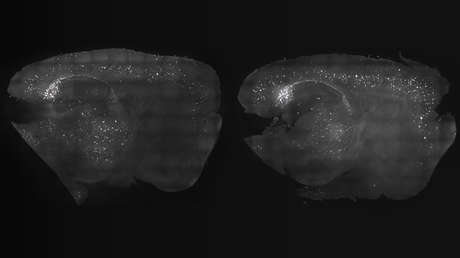

Un equipo de médicos y biólogos madrileños, coordinado por María Llorens Martín, estudió microscópicamente los cerebros de 58 personas recién fallecidas, 45 de las cuales habían padecido de alzhéimer y 13 murieron sanos. Su edad variaba entre los 43 y los 87 años.

En particular, investigaron el hipocampo, la estructura que se esconde en el interior del cerebro y define nuestras emociones y recuerdos, y que está presente en todos los mamíferos. Ya previamente se había registrado en algunas especies el fenómeno de la neurogénesis hipocampal adulta, o la creación de nuevas células en esa parte del cerebro. Sin embargo, hasta ahora se debatía si en los seres humanos adultos existía la capacidad de producir nuevas neuronas.

De este modo, los científicos lograron hallar, en los cerebros examinados, células nerviosas recién nacidas y todavía no desarrolladas plenamente.

Descubrieron que, a pesar de que la intensidad de la neurogénesis disminuye con la longevidad, el proceso no concluye totalmente ni aun en la edad senil. Así, los científicos detectaron neuronas emergentes en el hipocampo de una persona de 87 años.

En contrapartida, sí se registró una reducción drástica en la aparición de nuevas neuronas en humanos que sufrían de alzhéimer, lo que abre nuevas perspectivas para el tratamientos de las enfermedades del espectro demencial.